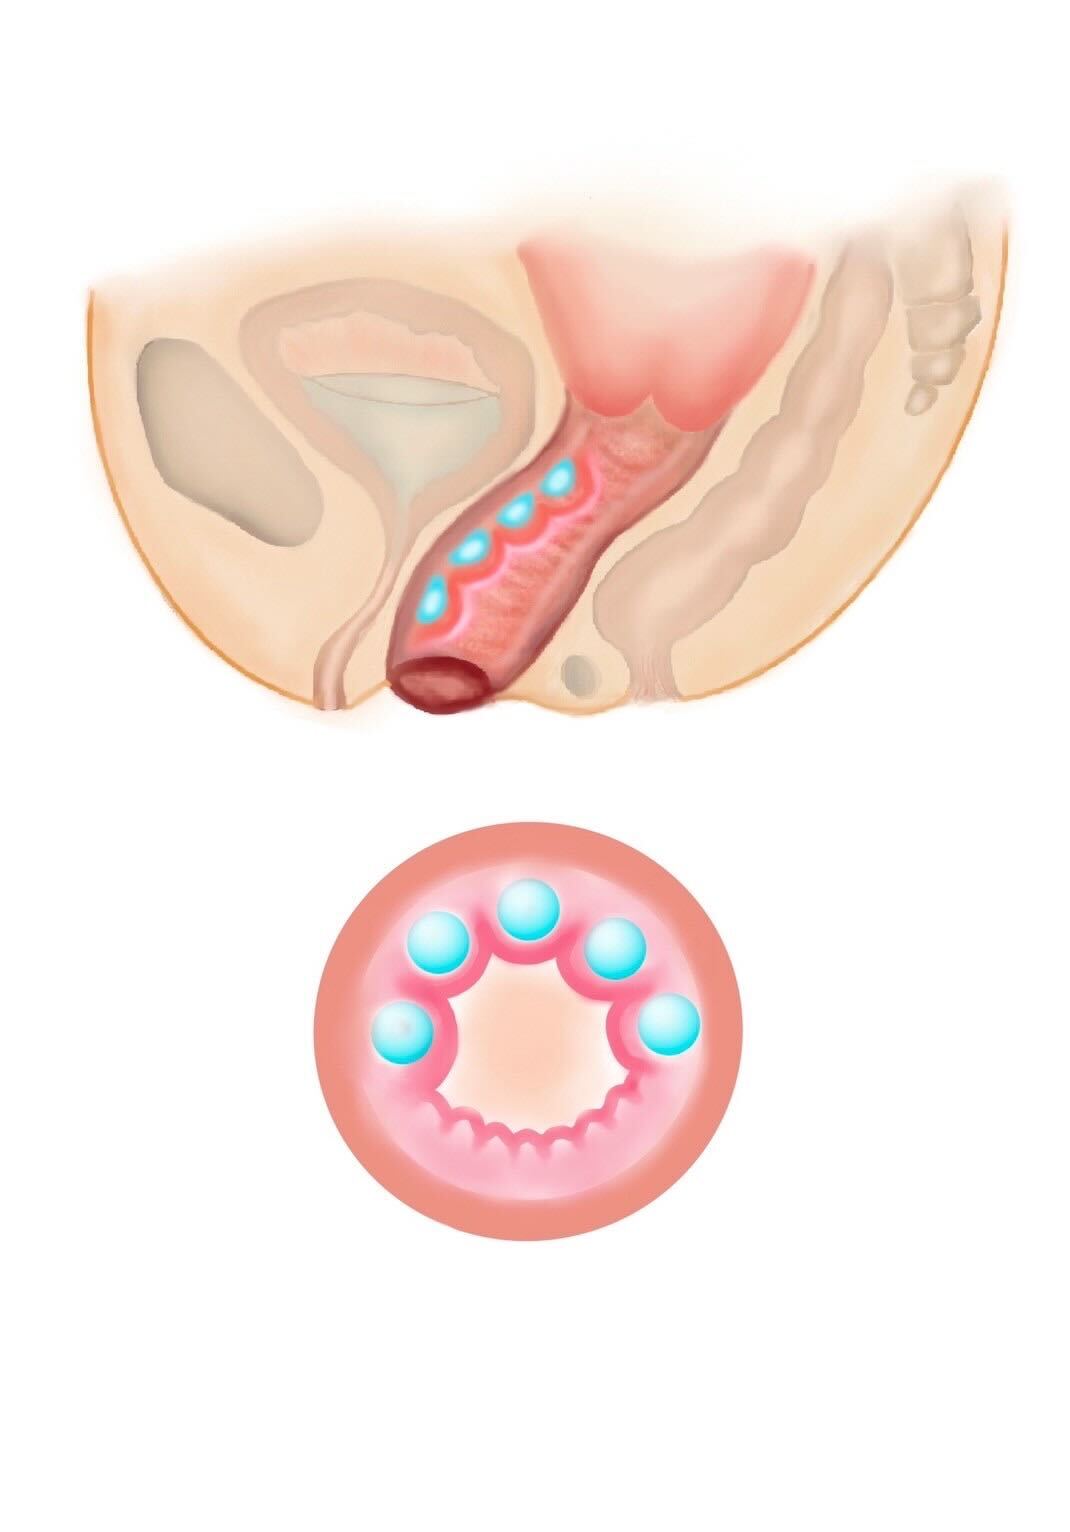

加齢や出産が原因で低下した膣圧を改善する治療です。ヒアルロン酸を注入する部位や量を変えることで、膣内の好きな部位を狭くし自由に膣圧を高めることが可能です。治療直後より効果が実感できます。性行為時の満足度を高めたり、女性として自信が持てたり、尿漏れを改善するなどの効果があります。当院では、膣治療を専門的に行なっているため、お悩みに合わせたカスタム注入が可能です。 ヒアルロン酸は少しずつ体内に吸収され、1.2年でなくなりますので、効果を持続させたい方は追加の注入が必要になります。 効果を持続させたい方は膣内の脂肪注入をご検討ください。

① 部分注入(Gスポット周辺に注入)

Gスポット周辺にヒアルロン酸を注入し、膣粘膜に厚みをもたせる方法で、性感帯の膨らみを作ることで、刺激を感じやすくなる可能性があります。膣のゆるみよりも、快感度の向上を希望する方に適しています。

② 円周注入(膣の締まり感向上)

膣の周囲に均等に注入し、膣壁にボリュームをもたせる方法で、膣粘膜のハリを高め、膣のフィット感を向上させる可能性があります。

出産後に膣のゆるみを感じる方、膣のハリ不足が気になる方に適しています。

③ 多層注入(バランスのとれた名器形成)

膣の内〜外側にかけてヒアルロン酸をバランスよく注入する方法で、膣のハリと潤いを向上させ、より自然な仕上がりを目指す注入方法です。

膣のフィット感と潤いを同時にサポートしたい方に適しています。

④ 立体層状注入(名器形成を目的とした施術)

膣内の構造を立体的に整え、締まり感と性感向上を目的とした施術で、ヒアルロン酸を膣内に立体的に注入することで、ボリュームを調整し、より高い密着感やフィット感を目指します。

より強い締まり感やパートナーとの密着感を求める方に適しています。

また、ご希望に応じて、巾着、タコつぼ、数の子天井、俵締め、みみず千匹などと称される施術方法にも対応しております。